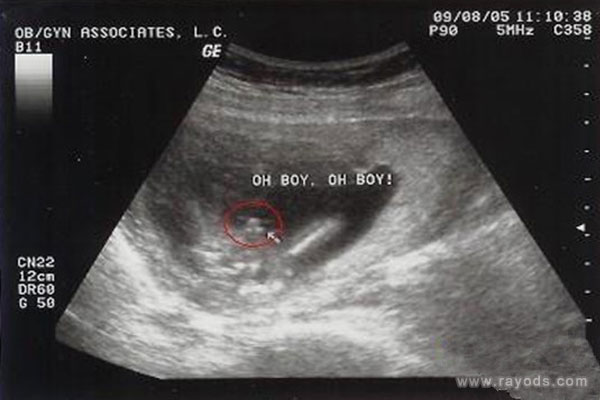

网传,四维3个亮点是男孩,四维3条白线是女孩。四维彩超单子,必须是照到胎儿宝宝的下半身,如果彩超图像有三条线的标志,那正是女孩的小***,是非常明显的女性特征;如果彩超图像有突出的东东西,有的说是圆圆的上面还有个尖尖的,那正是男孩特有的标志。

网友:四维彩超单子上,真的男孩女孩的答案,一般怀男孩单子上可以看到3个亮点,胎儿两腿中间有小突起。